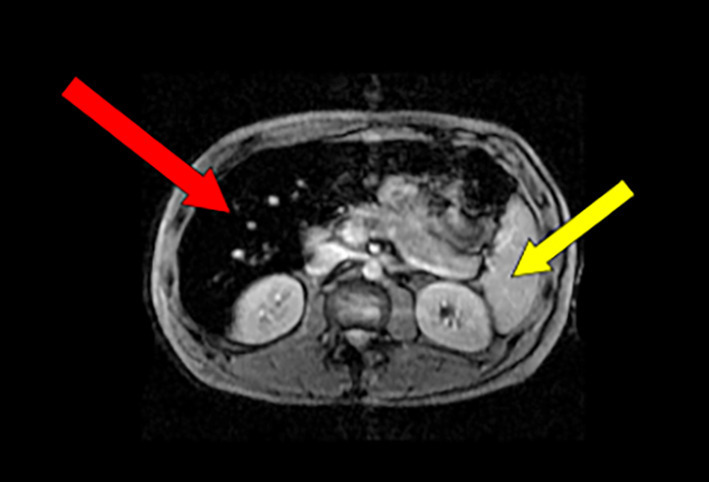

Visualiser en la quantifiant la surcharge en fer. Si le taux de ferritinémie, rigoureusement interprété, fournit une information de qualité sur l’intensité de la surcharge, seule une vision quantifiable apporte une certitude. Un foie « noir » correspond à une surcharge massive (fig. 2 ).

En préciser le mécanisme. La surcharge hémochromatosique donne, typiquement, une image de foie « noir » et de rate « blanche » (dénuée de fer), en rapport avec le déficit en hepcidine (hormone de régulation systémique du fer). Celui-ci est en effet à l’origine d’un afflux de fer dans les hépatocytes, provenant à la fois de son hyperabsorption digestive et de sa libération excessive à partir de la rate (où se poursuit physiologiquement la dégradation des globules rouges).

À l’inverse, une surcharge en fer « iatrogène » provoque une surcharge splénique, donc un aspect de rate « noire » car le fer provenant de la destruction des globules rouges (cas de la surcharge transfusionnelle) ou de la forme chimique du fer injecté (si supplémentation excessive en fer) est stocké essentiellement au niveau des macrophages dont la rate est particulièrement riche.